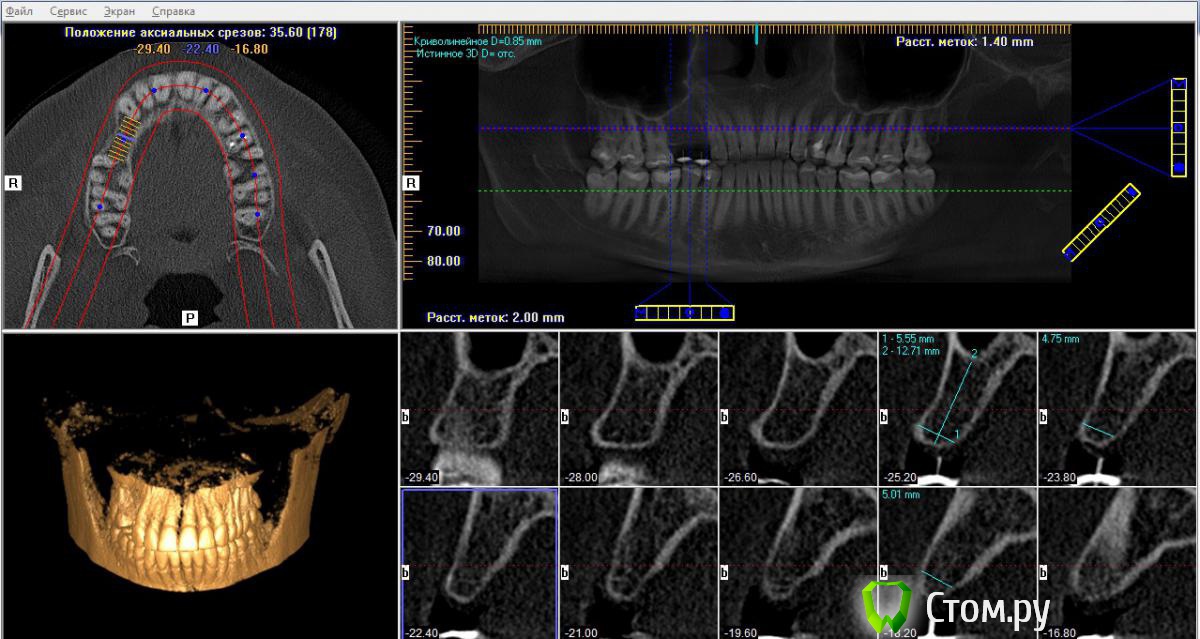

Alexey Doc Опубликовано 11 июня, 2014 Поделиться Опубликовано 11 июня, 2014 (изменено) Здравствуйте коллеги!Планируется имплантация в области утерянных около 5-ти лет назад зубов 1.4, 1.5. в максимально правильной позиции относительно протетической плоскости. Система имлантататов Implantium с минимальным диметром 3.6.Сделан wax-up, рентгенконтрастный шаблон.Кто какие варианты решения данной клинической ситуации предпринял бы?Собственные задумки:1) 2 имплантата 3.6х10 + НКР ( ауто на витки+мп3+ эволюшн ) 2) МПК + отсроченно 2 имплантата 3.6х103) один имплантатат 4,0х10 + НКР в позиции 1.5 (ортопедическая конструкция с мезиальной консолью), учитывая отсутствие права на ошибку при позиционировании имплантатов по мезиодистальным параметрам.( измерения на КТ и на модели совпадают )Результаты КТ исследования прилагаю: Изменено 11 июня, 2014 пользователем Alexey Doc Ссылка на комментарий